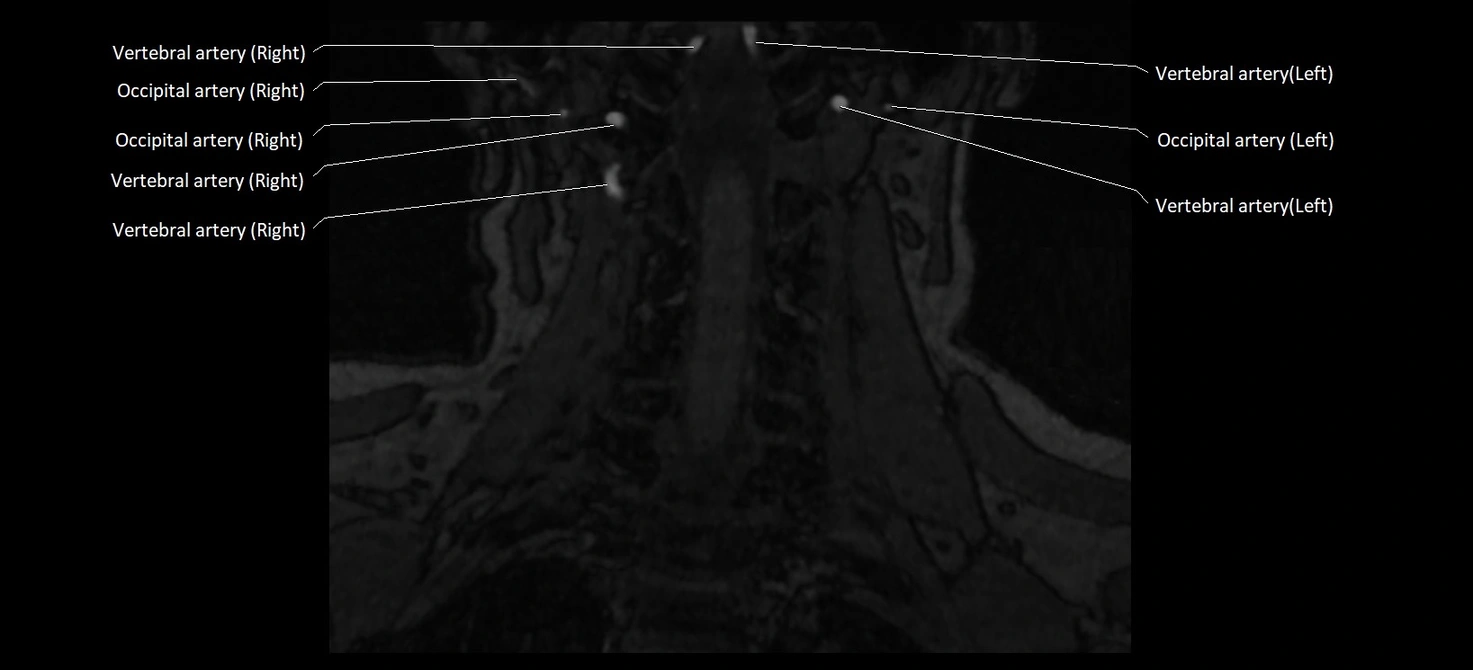

MRI images

image